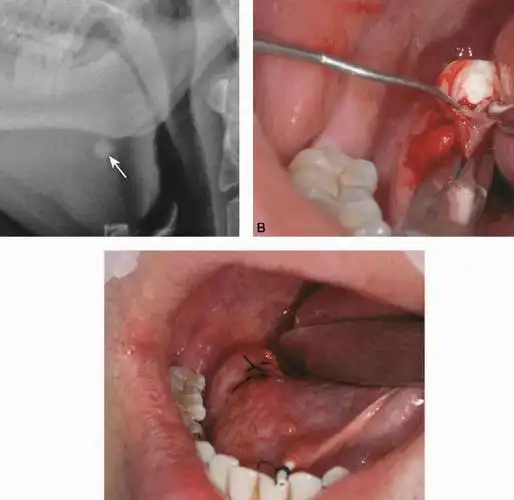

疾病百科 医学名词 下颌下腺结石的现代治疗方法缝合下颌下腺导管及口